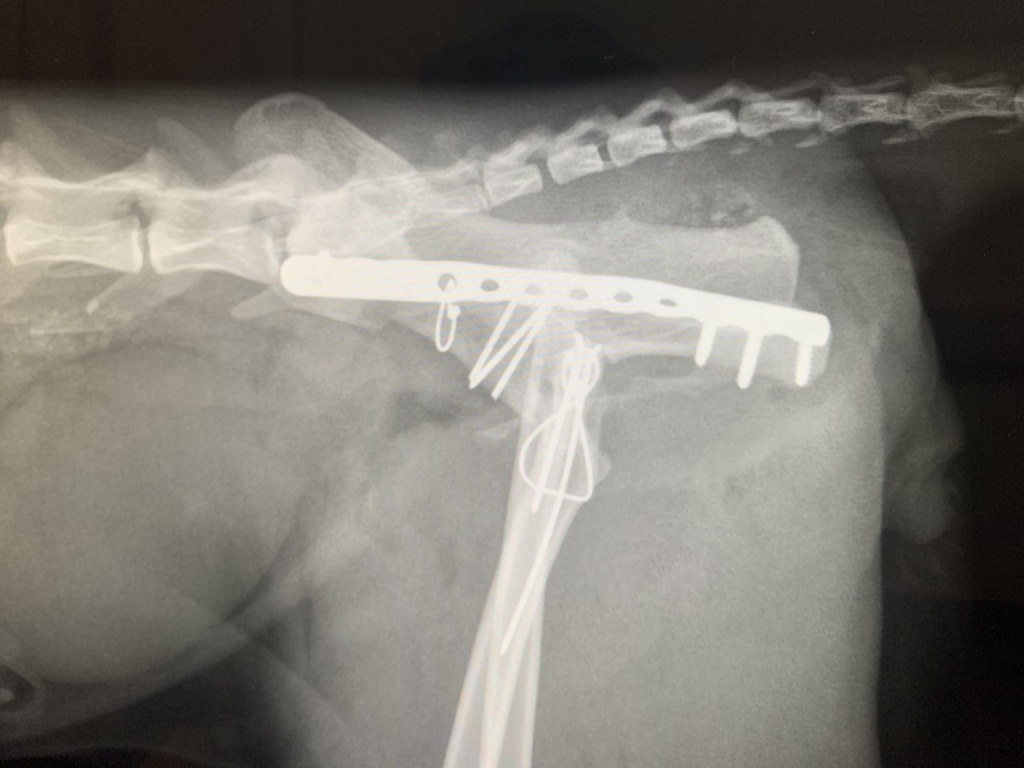

His pelvis was wired, screwed and plated back together in an intricate two-hour operation led by advanced small animal practitioner Jon Mills at West Midlands Veterinary Referrals, near Burton-on-Trent in Staffordshire.

“The right acetabulum was fractured very badly. Most of the acetabulum stayed with the ischium; the cranio-ventral part stayed with the ventral iliac wing and the rest of the iliac wing was attached to the sacrum.

“Fixing it required numerous pins and wire, and this was all buttressed with a 2.4mm locking plate.

“There were a few minor comminutions. A trochanteric osteotomy, fixed with two pins and wire, facilitated accurate reduction which was pleasing.

“There were three pins and a cerclage wire used for initial reduction and the plate had three screws proximal and three distal.